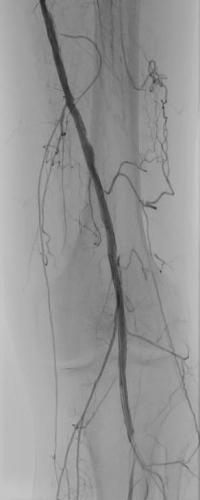

71-year-old man admitted due to critical ischemia of the right lower limb, with painful and non-healing necrosis of the first and second fingers. Diagnosis showed total occlusion of the tibial and dorsal arteries on the right side (Figure 1).

Procedure summary

Angioplasty was performed for 3 minutes in the right posterior tibial artery, in the tibiofibular trunk and in the fibular artery. Angioplasty of the distal PTA and lateral plantar artery was performed with Passeo™-18 Lux™ DCB.